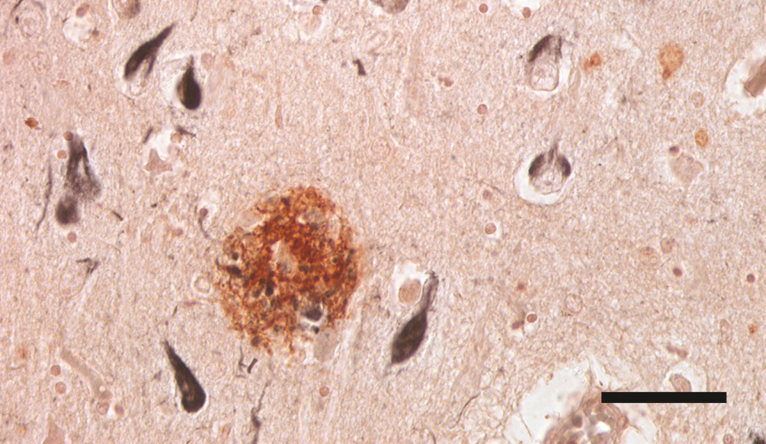

新闻图片2

2. AD 的典型神经病理学特征包括老年 (Aβ) 斑块 (红棕色) 和神经原纤维 (Tau) 缠结 (黑色)